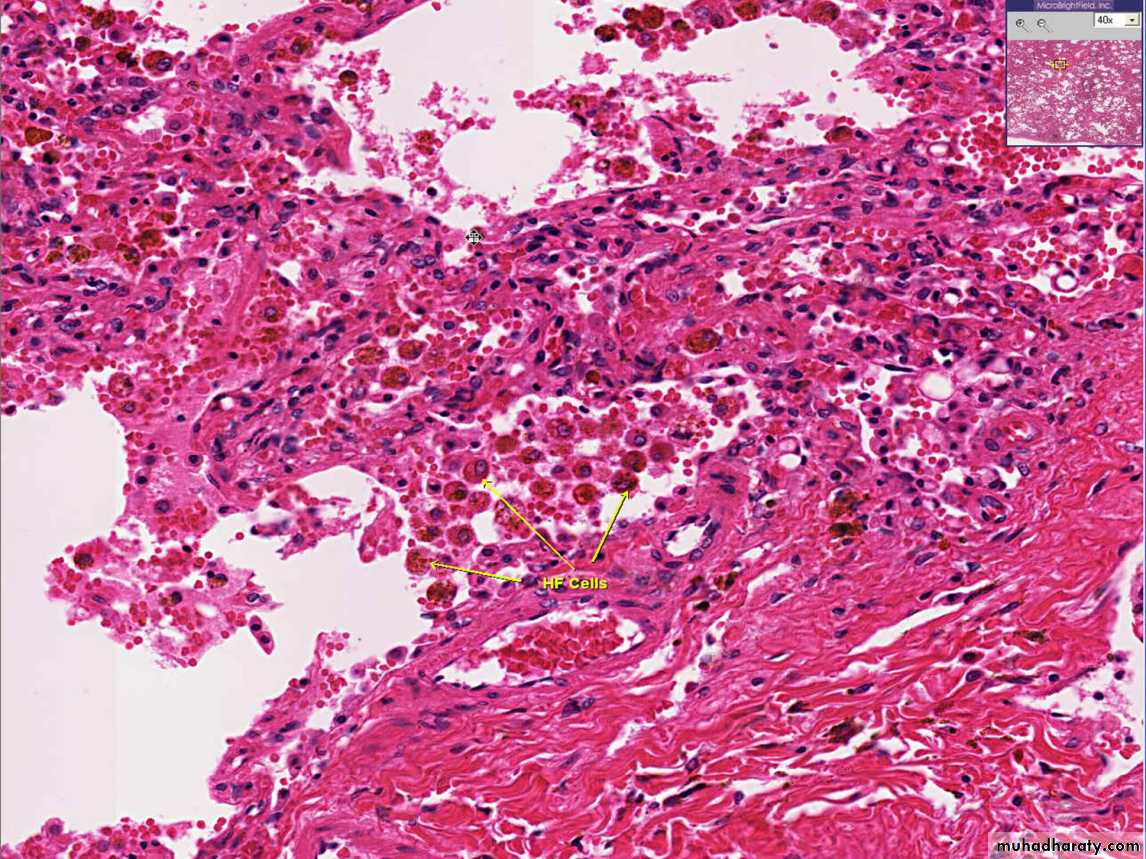

-2Chronic pulmonary congestion

Thickened & fibrotic septa

Alveolar spaces contain hemosiderin-laden macrophages (“heart failure cells”) derived from phagocytosed red cells.

Fig:CHRONIC PASSIVE HYPEREMIA/CONGESTION, LUNG: heart failure cells

Fig:Special stain for haemosiderin (prusian blue) for heart failure cells